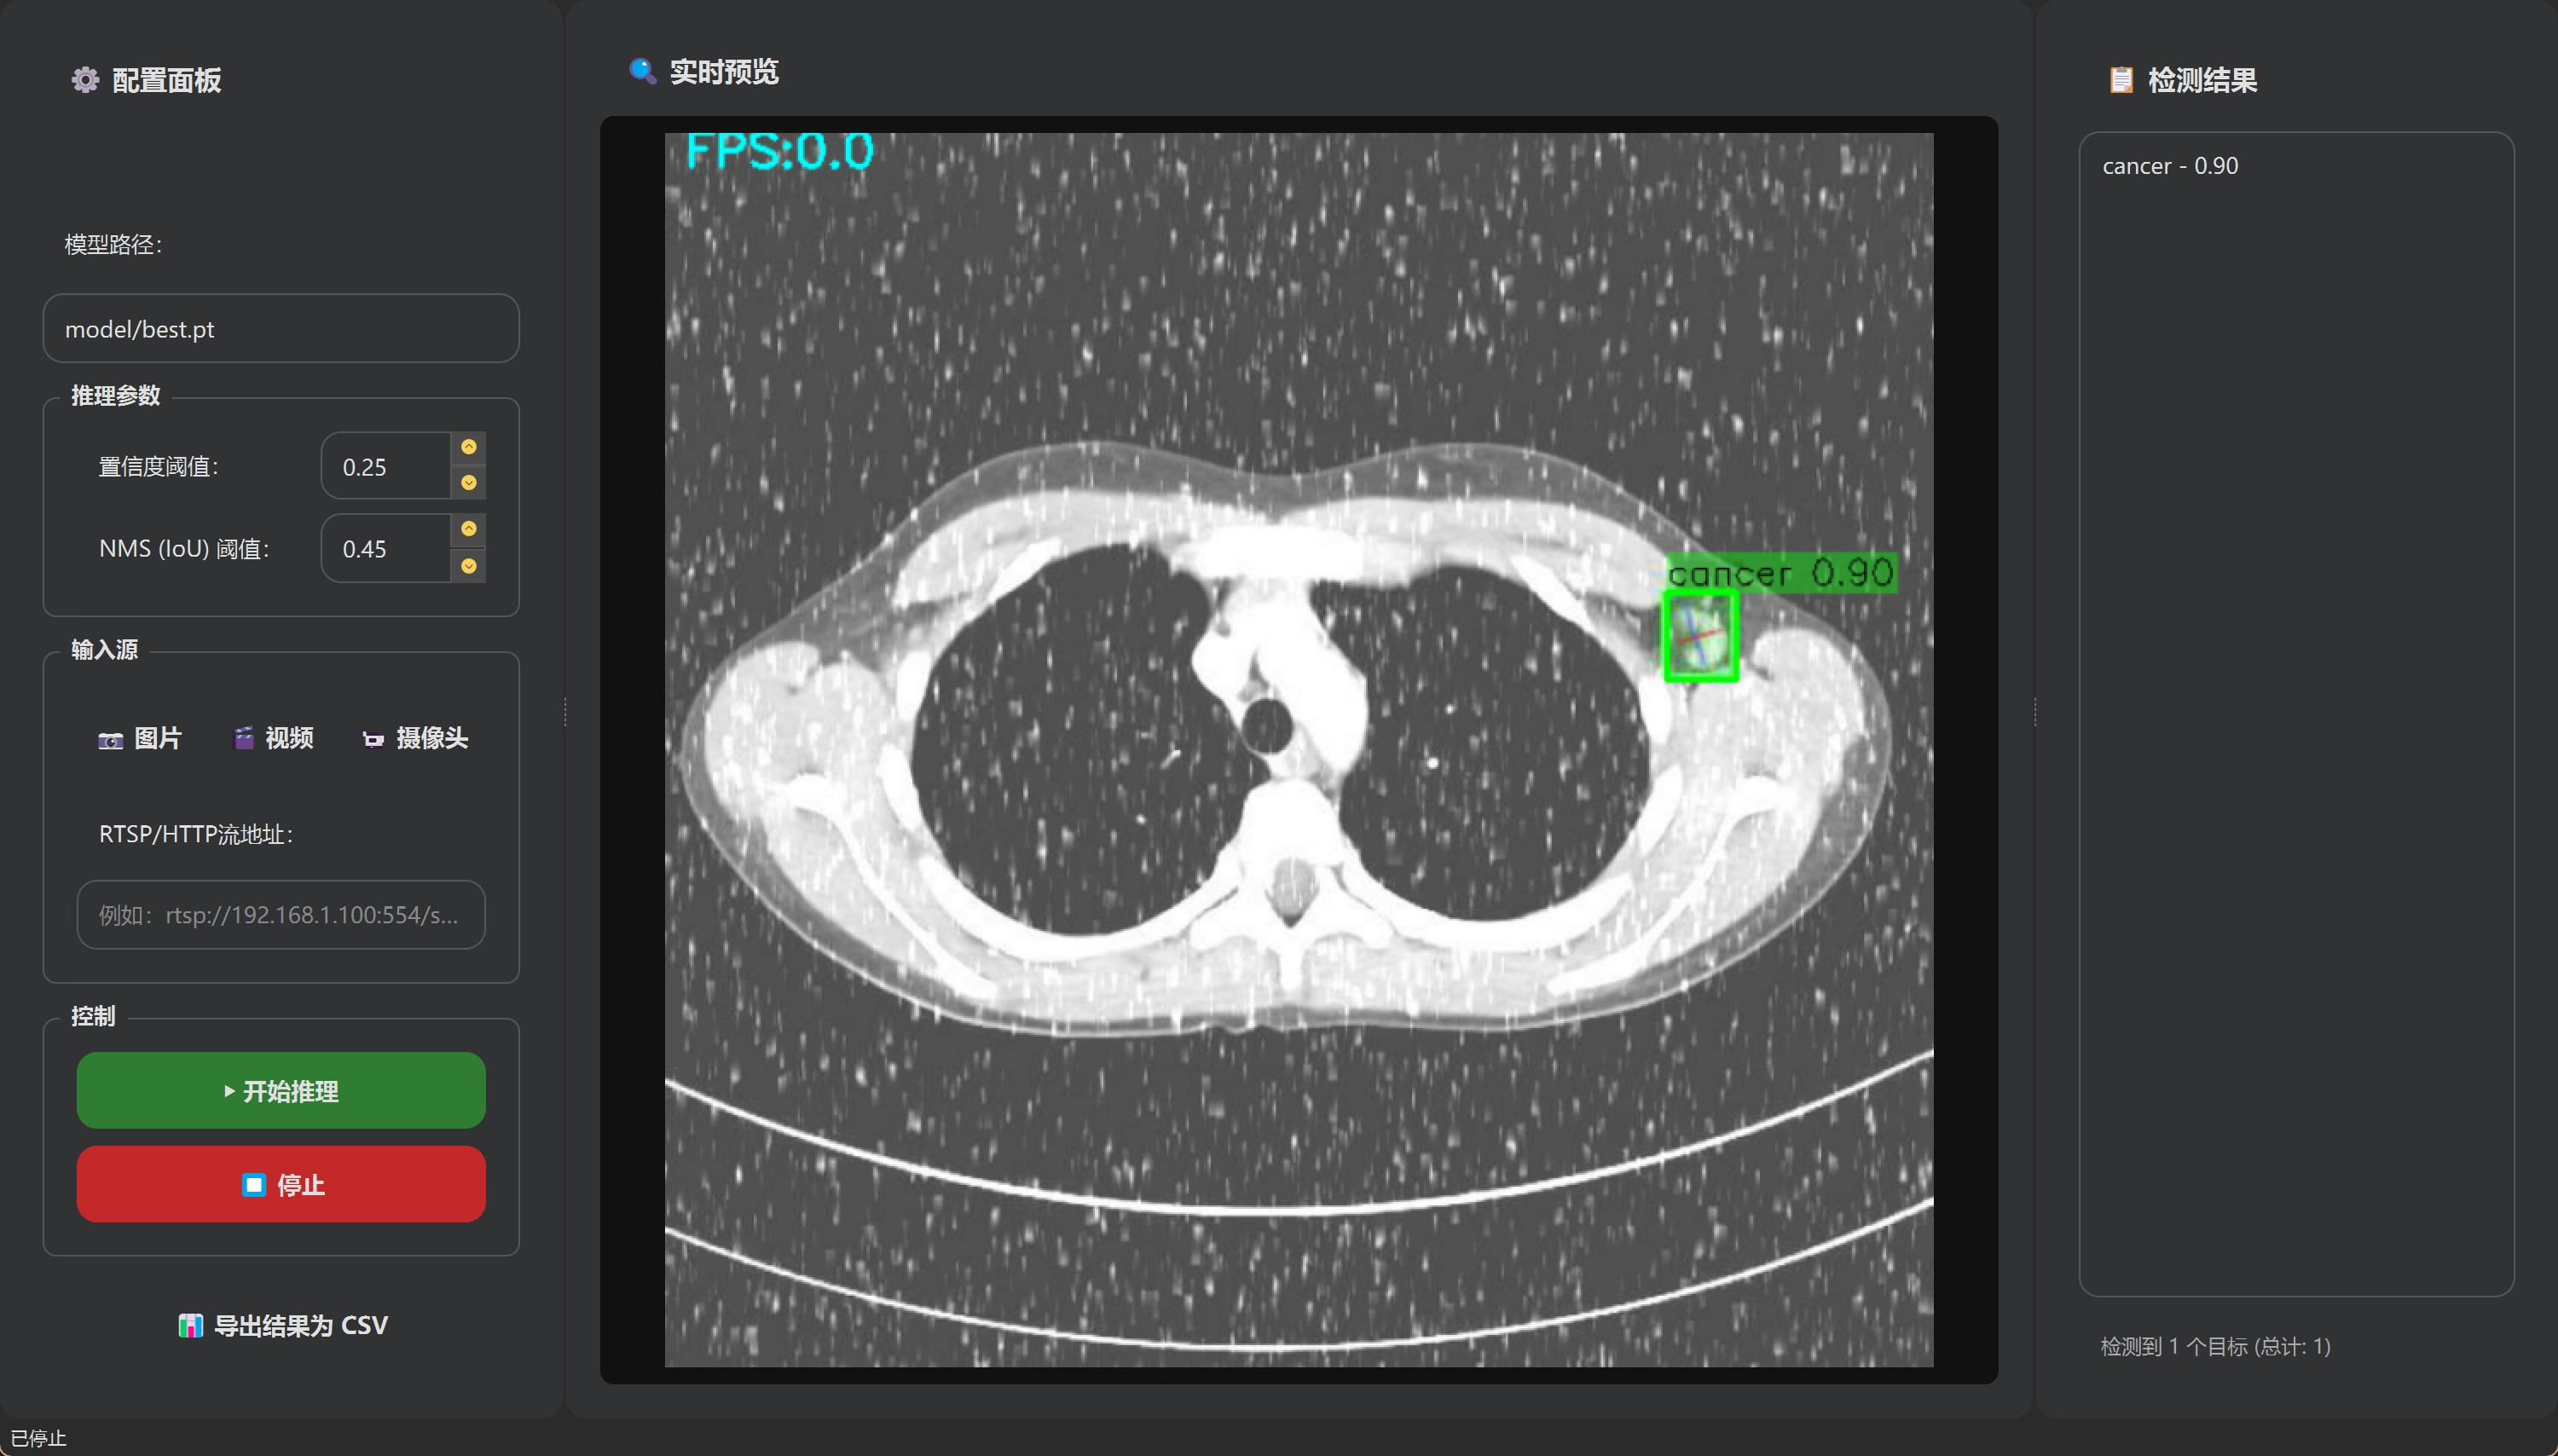

✨ 4、效果演示